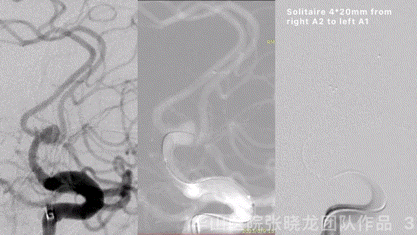

Figure 3 GIF. General heparinization was performed. An size 4.5*4.3mm, neck 2.9mm, proximal parent artery 2.9mm, distal parent artery 2.0mm. 6F Envoy DA was placed into left ICA cavernous segment. Nimodipine 1ml was administered. First advanced a C-tipped Freepass-21 into left A2, then SL-10 into right A2. Tried to exchanged SL-10 to another Freepass-21, Rebar-18 and Prowler plus, all failed. Withdrew the Freepass-21 of left A2 segment. A Frepass-21 was place at the right A2 segment, then navigated a SL-10 into the left A2 via a V-18 for support. A Solitaire 4*20mm was deployed from right A2 to left A1.

图 3 GIF. 行全身肝素化。测量动脉瘤大小4.5*4.3m,瘤颈2.9mm,近端载瘤动脉直径2.9mm,远端载瘤动脉直径2.0mm。将6F Envoy DA导引导管置于左侧颈内动脉海绵窦段,经导引导管给予尼莫地平1ml。将Freepass-21微导管(头端塑C弯)后超选至左侧大脑前动脉A2段,SL-10微导管超选至右侧A2。选用另一枚Freepass-21微导管交换SL-10微导管,导引导管不能兼容。更换Rebar-18和Prowler plus微导管均不能兼容。遂撤回左侧大脑前动脉Freepass-21。将Freepass-21微导管置于右侧A2,在V-18支撑下将SL-10置于左侧a2。选用Solitaire 4*20mm于右侧A2至左侧A1释放。